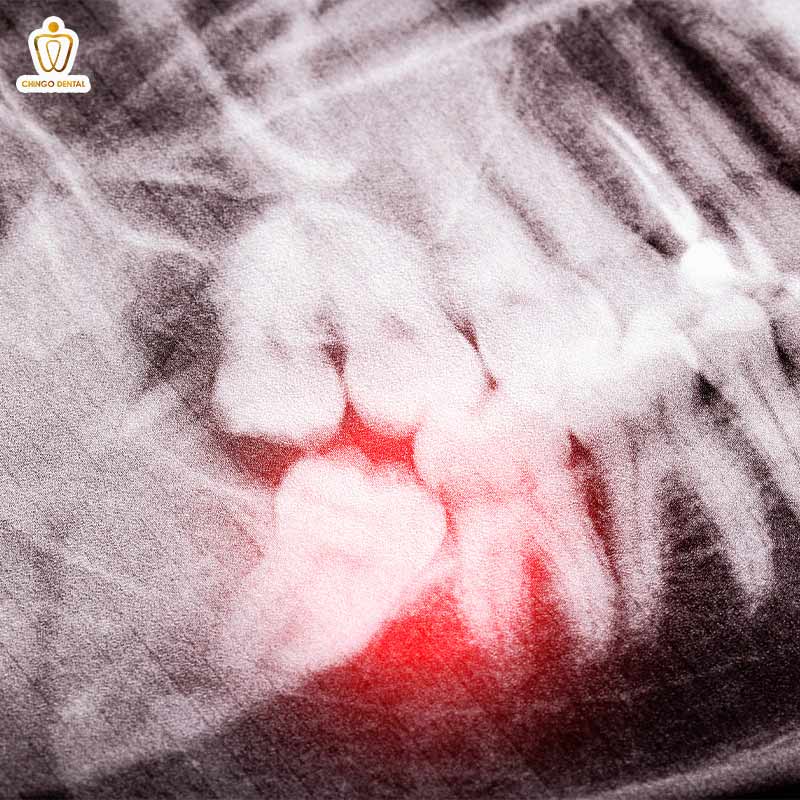

Không chỉ đối mặt với sự tấn công của vi khuẩn, răng số 7 còn thường xuyên bị “hàng xóm” là răng khôn gây hấn. Tình trạng răng khôn mọc lệch đâm vào răng số 7 giống như một quả bom nổ chậm trong khoang miệng. Khi chiếc răng khôn mọc ngang, nó tạo ra một khe hở “tử thần” giắt đầy thức ăn mà không một loại bàn chải nào chạm tới được.

Áp lực từ cú đâm này không chỉ gây đau nhức mà còn có thể làm tiêu xương, khiến chiếc răng số 7 bị lung lay đau nhức dù bản thân nó vốn dĩ rất khỏe mạnh. Đây là một trong những mối nguy hiểm thầm lặng nhất, vì khi bạn cảm thấy đau, có thể chiếc răng “trụ cột” này đã bị tổn thương nghiêm trọng ở phần chân răng.

Áp xe và viêm quanh chân răng

Khi sâu răng tiến triển quá sâu mà không được điều trị, vi khuẩn sẽ tấn công vào tủy và đi xuống chóp chân răng, tạo thành các ổ mủ (áp xe). Tình trạng này nếu để lâu sẽ khiến răng mất đi điểm tựa vững chắc, dẫn đến hiện tượng răng số 7 bị lung lay sau khi nhổ răng số 8 hoặc do viêm nhiễm lan rộng, khiến việc nhai nghiền gần như tê liệt.